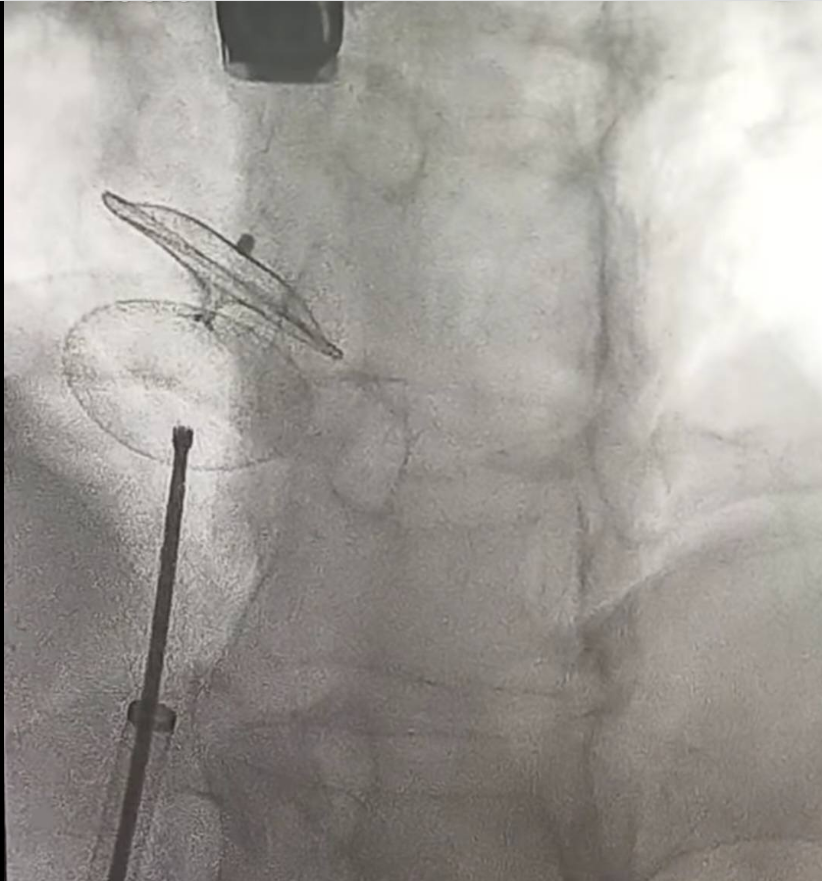

وقال الدكتور محمد خضر، استشاري أمراض القلب والأوعية الدموية، عن الثقب البيضاوي: "خلال هذا الأسبوع تم بفضل الله إغلاق الثقب البيضاوي بين الأذينين لمريض يبلغ من العمر ٤٥ سنة أصيب بجلطة مخية غير مفسرة ولا يعاني من أي أمراض أو عوامل خطورة أخرى".

وطالب الدكتور محمد خضر بالبحث عن إحتمالية وجود الثقب في هؤلاء المرضى، لمنع حدوث الجلطات المخية، يتم التشخيص بالموجات الصوتية للقلب والموجات الصوتية للقلب عن طريق المنظار، والعلاج في الحالات التي تحتاج يتم عن طريق القسطرة.